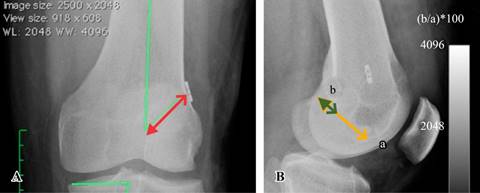

Radiográficamente evaluamos en el fémur: el ángulo de inclinación del túnel femoral, tomando una línea recta que pasa por el centro de la diáfisis femoral y otra línea que pasa por el centro del túnel femoral,4 el sitio de inserción con respecto a la línea de Blumensaat en forma porcentual,5 tomando la longitud de la línea de Blumensaat en cm y luego midiendo de la cortical posterior la distancia en cm al centro del túnel femoral y la distancia transósea del fémur medida desde el intercóndilo hasta la cortical femoral a la altura del botón femoral o proyectando una línea a través del centro del túnel femoral hasta la cortical femoral (Figura 1).

Figura 1: A) Ángulo de inclinación femoral (líneas verdes) y la distancia transósea (línea roja con dos flechas). B) Se marca la línea de Blumensaat (a) y la distancia del túnel femoral a la pared posterior (b).